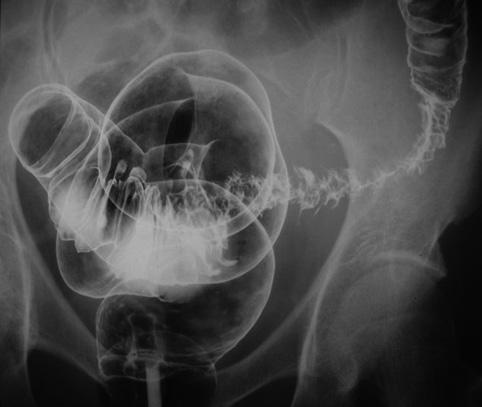

症例提示(所在地,施設名等): 佐賀県・ 佐賀県立病院好生館 (梶原先生からの提供症例)

疾患(病理主体)の分類憩室/憩室炎・憩室周囲膿瘍

部位(臓器別)大腸/S状

検査方法X-P